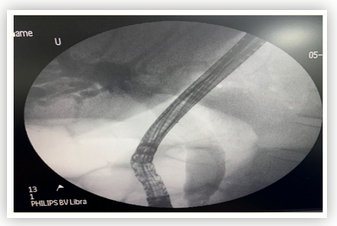

Endoscopical Retrograde Cholangiopancreatography. A Big Success? Multicentre Study in México

Mara Luz Terán Estrella, Morelos Adolfo García Sánchez, Mireya De La Fuente González, Ramón Armando Sánchez Tamayo, Pamela Navarro Hernández5, Oscar Manuel Cedillo Torres, Miguel Fernando Juárez Moyrón, Imelda Yasmín Palma Cortés, Antonio Tonatiuh Uribe Wittingham, Cristián Andrés González Vargas, Ana Fernanda Aburto Mariano, Mauricio Israel Flores Pazos, Juan David Martínez Gómez,Oliver Guillen Diego, Carlos Arturo Martínez Martínez, Beatriz Huiyu Li Gómez and Ángel Flores Montiel.